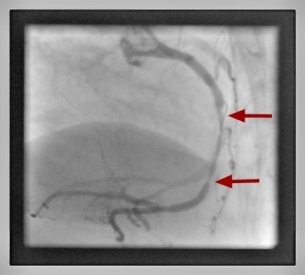

Percutane Koronarintervention Herzkranzgefäßeinengung Kardiologie Garbsen

Herzkranzgefäßeinengung

Bei Nachweis einer Verengung (Stenose) in einem Herzkranzgefäß erfolgt die Koronarintervention fast immer direkt im Anschluss an die diagnostische Herzkatheteruntersuchung. Unter Röntgenkontrolle wird zuerst über einen feinen Draht ein Ballon in die Engstelle platziert und mit hohem Druck geweitet (Ballondilatation).